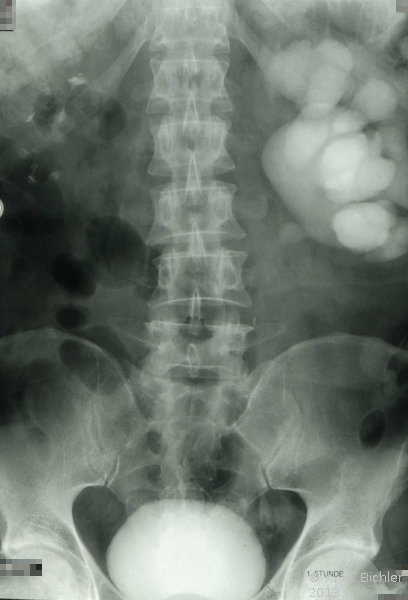

Auch minimalinvasive Methoden wie Ballondilatation bzw. Endopyolothomie (Cold knife incission) stehen zur Verfügung (Abbildung 14abcd).

Die Dilatation kann auch in Kombination mit Schnitt mit einem Spezialballon (Acucise Device ) erfolgen. Eine mehrwöchige postoperative Katheterschienung ist erforderlich (s. Abbildung 14d). Diese Methoden scheinen uns in Übereinstimmung mit Sigel und Rickwood et al eher für Jugendliche bzw. beim Erwachsenen geeignet bzw. zur Behandlung von Komplikationen (Obstruktionen) nach offen operativen Verfahren bei Ureterabgangsstenose.

Die endoskopischen Verfahren wie Endopyelothomie und die Dilatation durch Ballon eignen sich zur Erweiterung postoperativer Restenosen (Abbildung 14).